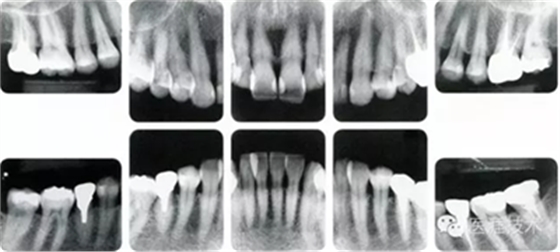

健康且正常的牙周組織臨床圖像

50歲女性的健康口腔內(nèi)部

圖為50歲女性,無特殊全身疾病,不抽煙。持續(xù)保養(yǎng)6年。無填充物等問題,依照患者本人要求持續(xù)觀察。牙周組織臉頰側(cè)雖見部分萎縮,但X線牙片顯示牙間無骨吸收現(xiàn)象,保持著比較健康的狀態(tài)。

18歲男性的健康口腔內(nèi)部

圖為18歲男性,無特殊全身疾病,不抽煙。持續(xù)保養(yǎng)10年。牙菌斑控制比以前好,因刷牙稍稍過度臉頰側(cè)有牙齦萎縮傾向,但牙齒及牙周組織仍保健康。